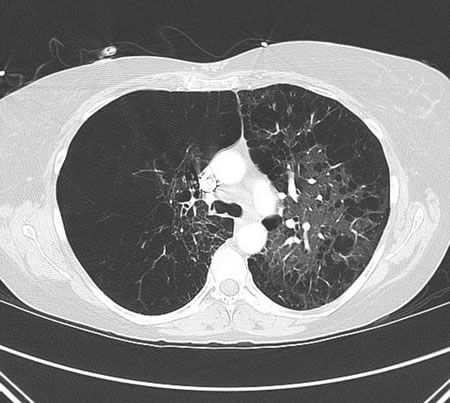

tomografia do tórax

Oferece uma melhor visualização que a radiografia torácica para o tipo e a distribuição dos danos no tecido pulmonar e formação de bolhas.[Figure caption and citation for the preceding image starts]: Tomografia computadorizada (TC) do tórax na DPOC: pulmão hiperinsuflado, alterações enfisematosas e aumento do diâmetro anteroposterior (tórax em tonel)Do acervo de Manoochehr Abadian Sharifabad, MD [Citation ends].

Em contraste com a DPOC relacionada ao tabagismo, a deficiência de alfa 1-antitripsina afeta principalmente os campos inferiores.

As diretrizes da Global Initiative for Chronic Obstructive Lung Disease (GOLD) recomendam a consideração de uma TC para pacientes com exacerbações persistentes, aqueles com sintomas que não correspondem à gravidade da doença nos testes de função pulmonar, aqueles com VEF₁ <45% do predito com hiperinsuflação significativa e aqueles que atenderem a critérios para rastreamento de câncer pulmonar.[1]

A TC de baixa dose anual é recomendada pela US Preventive Services Task Force para o rastreamento de câncer pulmonar nos pacientes com DPOC em decorrência de tabagismo.[72]

hiperinsuflação